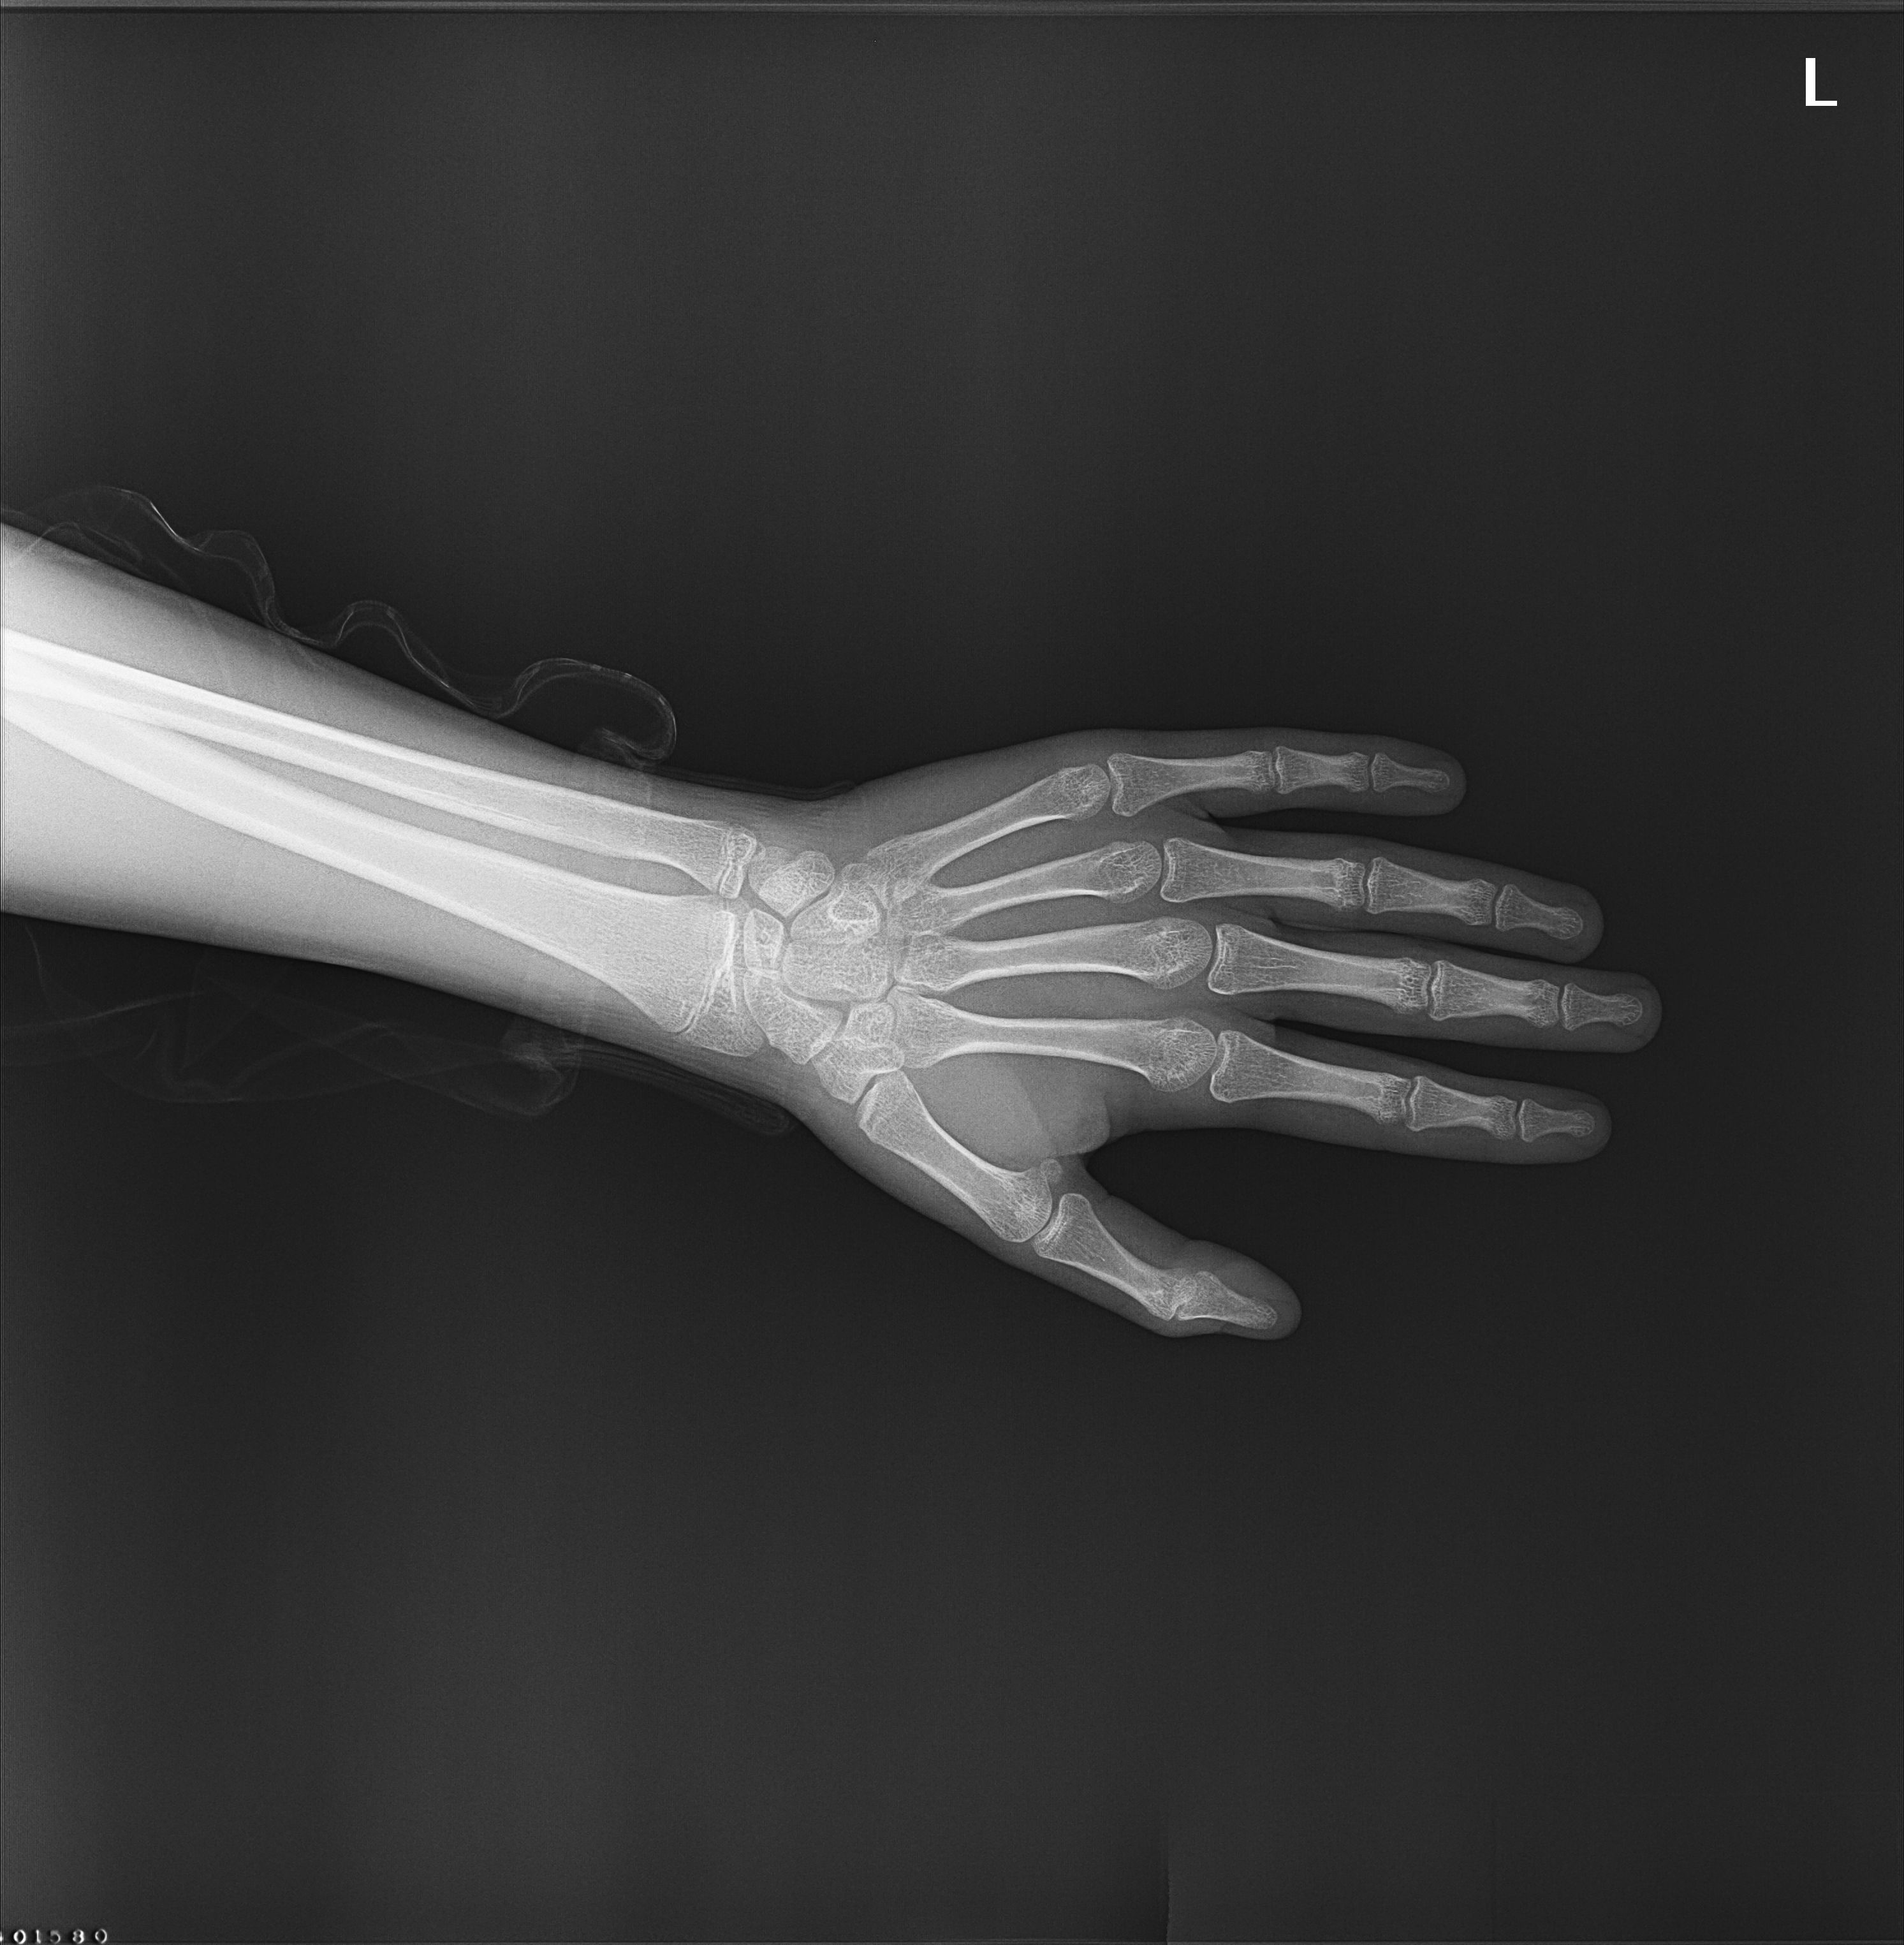

Merhaba arkadaşlar. 15 yaşındayım, 2005 doğumluyum. Tam çıplak ayak 1.77'yim. Boyum 7-8 aydır 2-3 CM uzadı. Büyüme plaklarım netten edindiğim bilgiye göre kapanmış gözüküyor. Aile hekimi "1.85 zorlarsın dedi" dedi, çocuk sağlığı doktoru ise vitaminin eksik dedi. Bilek röntgeni, kemik yaşı falan istedi. Pazartesi sonuçlarım çıkacak. Aynı boyda olduğum arkadaşlarımın çoğu 1.83'ü geçmiş ama benim böyle kalmam sinir bozucu. Sağlıklı beslendim. Babam, dayım, amcalarım uzunken böyle kaldım galiba. Bilek röntgenim aşağıda.

Eki Görüntüle 500709